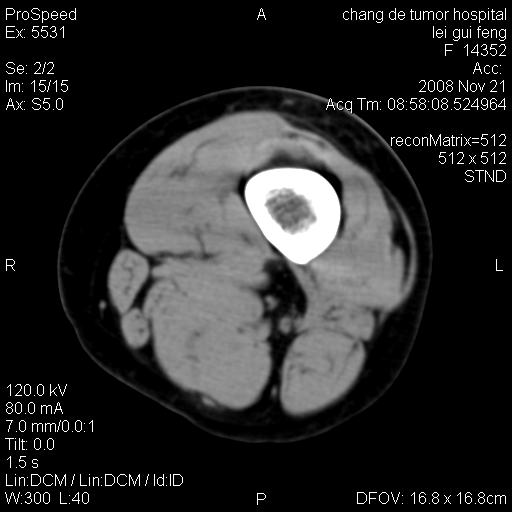

标题: CT16807:女 41 无不适 [打印本页]

标题: CT16807:女 41 无不适

考虑皮样囊肿可能性大

血管瘤可能

血管瘤

血管瘤可能性大!

黏液瘤或表皮杨囊肿

不排除横纹肌肉瘤可能。

血管瘤可能性大或畸胎瘤

考虑脂肪肉瘤

考虑血管瘤可能性大;不排除肉瘤可能。建议行活检。

脂肪肉瘤?

双是软组织肿瘤,病灶内多发钙化,另可见多量脂肪密度影,考虑畸胎瘤,血管瘤,不除外其他